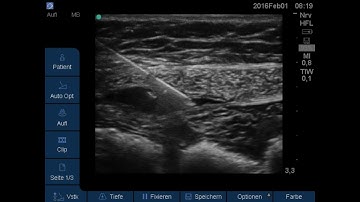

Rectus Sheath Block - A How-To Guide